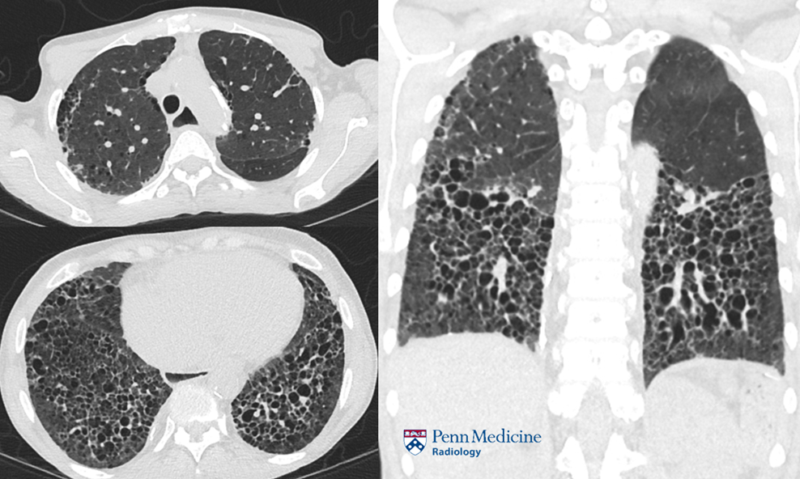

26-year-old man with neutropenia and dyspnea

Bahram Mohajer

A 26-year-old man with a history of familial nonischemic cardiomyopathy with heart transplantation presented with dyspnea on exertion and neutropenia.

Published Date: March 3, 2026

Tags:

Cardiac

,

CT

PET

Thoracic

X-Ray